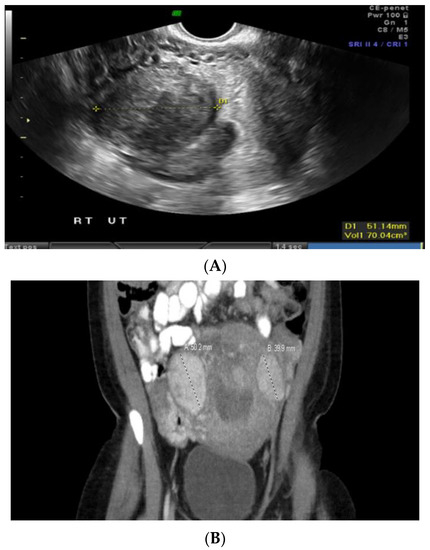

Case 2: A 34-year-old Black patient with a personal history of uterine fibroid and a family history of various cancers had an 8 cm submucosal uterine fibroid (Figure 2A). She underwent a total abdominal hysterectomy, left salpingo-oophorectomy, and right salpingectomy. Pathology revealed a leiomyoma with features of FH deficiency. Germline genetic testing showed a mutation in the NTHL1 gene, which is not associated with leiomyomas or an increased risk for cancer, and a variant of uncertain significance in the FH gene, c.1055G>A (p.Gly352Asp). This specific missense change, guanine to adenine at nucleotide position 1055, results in an amino acid change from glycine to aspartic acid at codon 352. At the time, there was not enough evidence to know whether this change disrupts protein function; this specific missense variant had not been reported by other laboratories, nor had it been reported in the literature in individuals with FH-related conditions. However, given the family history of renal cancer, the patient was advised to undergo screening for this malignancy. A subsequent abdominal ultrasound and computed tomography (CT) scan revealed a large mass extending from the left kidney (Figure 2B). A needle core biopsy showed a high-grade renal cell carcinoma with papillary features, suggestive of FH-deficient renal cell carcinoma. The patient underwent radical left nephrectomy and adrenalectomy, which confirmed high-grade renal cell carcinoma with poorly differentiated areas and focal sarcomatoid spindle cell change, suspicious for FH-deficient renal cell carcinoma. Left retroperitoneal lymph nodes were diffusely involved by metastatic renal cell carcinoma.

Figure 2. (A) Submucosal uterine fibroid. (B) Computed tomography (CT) scan-coronal section abdomen.